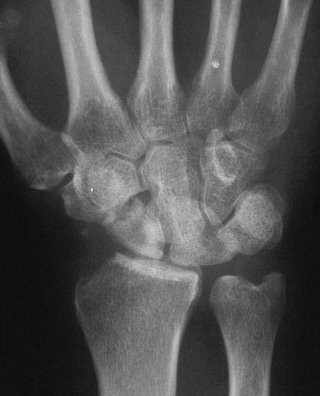

Clinical Example: Midcarpal instability following distal scaphoid excision

Distal scaphoid excision is gaining popularity as a treatment of scaphoid nonunion. It requires the strong radioscaphoid and radioscapholunate ligaments to maintain support of the remaining proximal carpus. In this case, the proximal carpus was destabilized by the effect of radial stylidectomy on these ligaments.

Clinically and by bone scan, this patient sustained a scaphoid fracture, but obviously had a preexisting distal pole cyst.